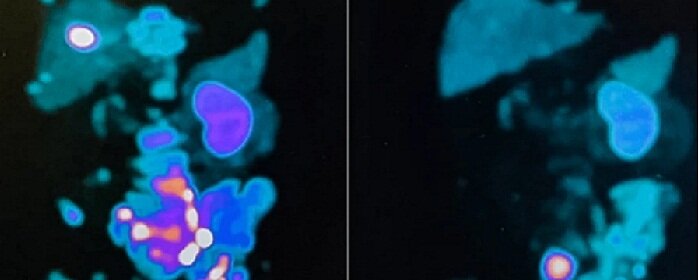

Кроме того, контрольное исследование выявило кардинальное снижение скорости накопления ПСМА-лиганда в метастазах.